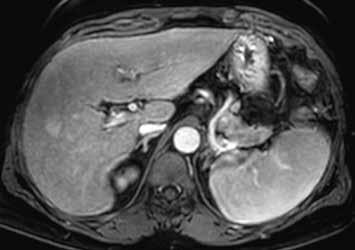

Zánětlivý HCA se v arteriální fázi homogenně sytí, v portovenózní fázi nedochází k vymývání kontrastní látky (obr. 3, 4). Při MR vyšetření můžeme zachytit „atoll sign“, tedy hyperintenzní lem kolem adenomu (obr. 5). Vyskytuje se postkontrastně až ve 25 % případů. V hepatobiliární fázi je tento adenom až ve 30 % hyperintenzní. Výrazné T2 hyperintenzity spojené s přetrvávajícím sycením mají senzitivitu 85–88 % a specificitu 87–100 % pro I-HCA.

HCA inaktivovaný HNF-1α obsahuje tuk, má proto nízký signál na všech sekvencích se saturací = „pseudo washout“, pseudoabsence sycení. V arteriální fázi se výrazně sytí, ale v portální a portovenózní fázi se většinou vymývá. V pozdní fázi je po podání specifické kontrastní látky hypointenzní (obr. 6–10).